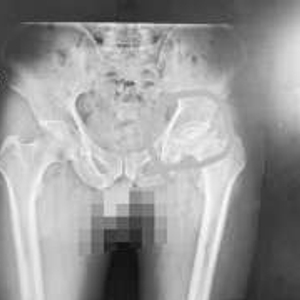

确诊  原来是股骨头坏死

“之前的骨科医生应该是受到了王女士的诱导,因为她见到医生就说自己是腰脱,导致医生忽视了其他骨科疾病的诊断。腿变短了,可能是股骨头出了问题。”蔡振存表示。通过股骨头部位的影像检测,王女士被确诊为股骨头坏死。通过股骨头置换手术,王女士的病得到了彻底解决。